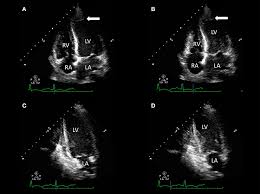

Peripartum Cardiomyopathy Circulation

Peripartum Cardiomyopathy Circulation from www.ahajournals.org

In the case of fulminant. Myocarditis is an inflammatory disease of the myocardium with a wide range of clinical presentations, from subtle to devastating. Current trends in diagnosis and treatment. Patients of suspected myocarditis are clinically evaluated to distinguish fulminant lymphocytic myocarditis from acute lymphocytic myocarditis. Myocarditis, also known as inflammatory cardiomyopathy, is inflammation of the heart muscle. • definition:myocarditis is an inflammatory disease of cardiac muscle. Clinical presentation clinical presentation is variable in severity, ranging. Journal of the american college of cardiology vol.

A position statement of the european society of cardiology working group on myocardial and pericardial diseases. In the case of fulminant. Myocarditis, also known as inflammatory cardiomyopathy, is inflammation of the heart muscle. Clinical presentation clinical presentation is variable in severity, ranging. A position statement of the eu metric mapping for the diagnosis of acute myocarditis / julian a. Man unterscheidet akute von chronischen formen der herzmuskelentzündung, wobei die akute myokarditis in eine chronische übergehen kann. Patients of suspected myocarditis are clinically evaluated to distinguish fulminant lymphocytic myocarditis from acute lymphocytic myocarditis. Myocarditis is an inflammation of the heart muscle (myocardium). Cardiomyopathies, myocarditis, and pericardial disease. Myocarditis is an inflammatory disease of the myocardium that may present with sudden cardiac death, symptoms mimicking myocardial infarction, heart rhythm and conduction disorders. Myocarditis can affect your heart muscle and your heart's electrical system, reducing your heart's ability to pump. Contemporary reviews in cardiovascular medicine. Symptoms can include shortness of breath, chest pain, decreased ability to exercise, and an irregular heartbeat.